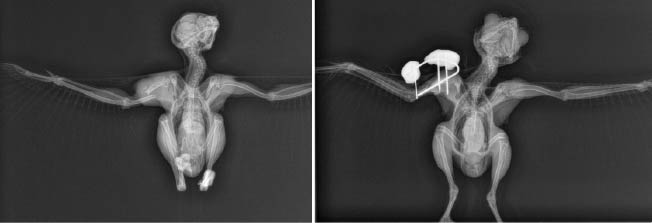

Les fractures sont toujours délicates à prendre en charge, mais celles qui concernent les ailes sont les plus critiques. Pour un oiseau sauvage, la qualité du vol doit être parfaite pour lui permettre de survivre dans son milieu naturel. Une fracture mal consolidée peut altérer le vol, même légèrement, et cette différence devient rapidement un véritable handicap. Certaines espèces, comme les faucons, dépendent d’un vol précis et rapide pour chasser efficacement. Les grands migrateurs, eux, doivent parcourir de très longues distances. Si leur vol est moins performant, ils se fatiguent beaucoup plus rapidement et leurs chances de survie diminuent fortement. Depuis plusieurs mois, le centre observe une augmentation importante des collisions avec des véhicules. Face à ces situations souvent complexes, SOS Faune Sauvage travaille depuis un an avec une vétérinaire spécialisée en chirurgie orthopédique, qui peut intervenir sur des cas particulièrement difficiles. Grâce à ces compétences, des opérations lourdes et très techniques peuvent aujourd’hui être réalisées sur des oiseaux qui, auparavant, ne pouvaient pas être soignés.

Des chirurgies suivies d’une longue rééducation

Après l’opération, les soins se poursuivent avec une étape essentielle : la rééducation. Les oiseaux opérés bénéficient d’un suivi avec un vétérinaire pratiquant l’ostéopathie et la physiothérapie (correspond à de la kinésithérapie) afin de les aider à retrouver progressivement mobilité et capacité de vol. Les fractures complexes demandent souvent un temps de guérison et de rééducation particulièrement long (environ 3 mois), avant qu’un retour à la vie sauvage soit envisageable. Depuis un an, les résultats obtenus grâce à ces chirurgies et à ce suivi sont très encourageants et permettent de donner une nouvelle chance à des oiseaux gravement blessés.